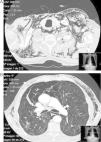

A 75-year-old male with GOLD grade IV COPD, who had undergone upper right lobectomy for pulmonary epidermoid carcinoma, came to our emergency room due to COPD exacerbation. The patient was admitted to hospital and evolved favorably during the first 72h. On the fourth day of hospitalization, after the exertion of defecating, he presented dyspnea and left pleuritic chest pain. Upon examination, subcutaneous emphysema was found in the apical region of the left hemithorax. Chest radiography confirmed the presence of air in the subcutaneous tissue. The patient was treated with rest, oxygen therapy and analgesia, but the subcutaneous emphysema extended throughout the thorax, face, eyelids and abdomen. Thoracic CT showed the presence of PM and massive SE with no evidence of pneumothorax, pulmonary emphysema and post-surgical absence of the left upper pulmonary lobe (Fig. 1). After 48h, the patient presented symptoms of thoracic discomfort, sweating and presyncope, and electrocardiogram demonstrated paroxysmal atrial fibrillation. In this situation, it was decided to insert a right subcutaneous drain (Fig. 2). The patient's symptoms improved almost immediately, and the drain was able to be withdrawn 5 days later. Over the following 6 months, the patient presented no relapse.